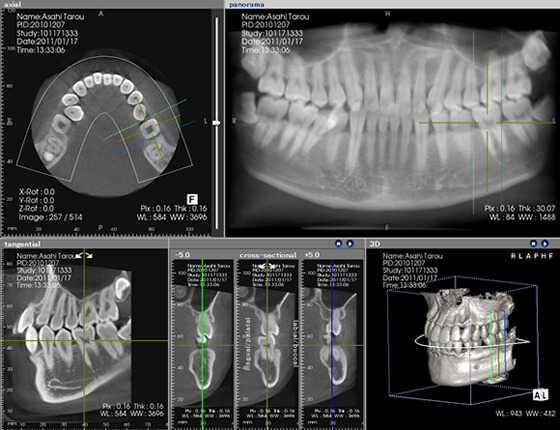

歯周病は顎の骨を溶かす病気ですので、CTやレントゲン検査を行い、顎の骨の状態を確認します。